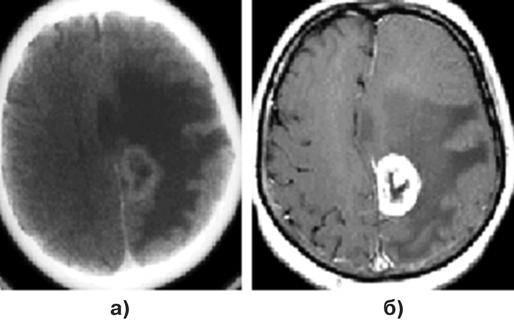

Диагноз подтверждается при МРТ, причем для визуализации небольших метастазов исследование целесообразно выполнять сразу с контрастированием препаратом гадолиния. Обычно метастазы выглядят как зоны повышенного сигнала как в Т1, так и Т2 режимах МРТ (рис. 1–3).

Рисунок 1. Метастаз аденокарциномы в медиальные отделы теменной доли слева:

а — КТ с контрастным усилением, аксиальная проекция; б — МРТ (Т1 режим) с контрастным усилением, аксиальная проекция